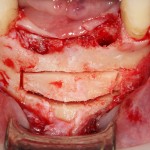

а для бокового отдела нижней челюсти — сам Б-г велел все делать через одну рану:

Другими словами, друзья, старайтесь максимально уменьшить размер доступа, но не в ущерб хорошему обзору, разумеется. Разрез и формирование доступа — это всегда компромисс. С одной стороны — размер раны, с другой — нормальный обзор.